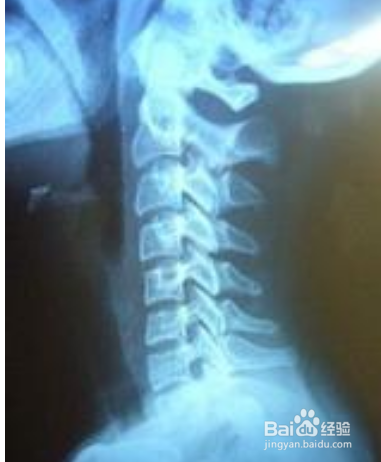

在医学上把这一向前的弧形凸起称为颈椎的生理曲度。通过X线片上的颈椎显像:沿此曲度走行,在各个颈椎椎体后缘都有形成的连续、光滑的弧形曲线,医学上称之为颈椎曲度。颈椎生理曲度的存在,能增加颈椎的弹性,减轻和缓冲重力的震荡,防止对脊髓和大脑的损伤。由于长期坐姿、睡姿不良和椎间盘髓核脱水退变时,颈椎的前凸可逐渐消失,甚至可变直或呈反张弯曲,即向后凸,成为颈椎病X线上较为重要的诊断依据之一。